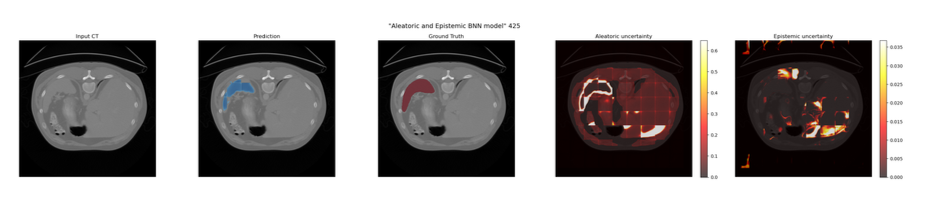

Model D and E

Bayesian Neural Network Model (Model E)

Epistemic Uncertainty: A 3D Dropout layer (p=0.5) was introduced at the bottleneck. During inference, Monte Carlo (MC) Dropout was utilised by keeping the model in training mode and executing 20 forward passes. Epistemic uncertainty was calculated as the variance of predictions across these passes.

Aleatoric Uncertainty: The network was split into a dual-head decoder after the bottleneck. The Prediction Head yielded the class probability map, while the Variance Head output a log-variance map (predicting the logarithm ensures positive variance).

In clinical practice, a model that simply outputs a prediction is insufficient; clinicians need to know *when* the model is unsure. By building a dual-head Bayesian Neural Network into this pipeline, the model generates diagnostic heatmaps that isolate Epistemic uncertainty (model ignorance) from Aleatoric uncertainty (CT acquisition artifacts).

- Bayesian Attention U-Net: Upgraded to quantify uncertainty and output Aleatoric and Epistemic heatmaps.